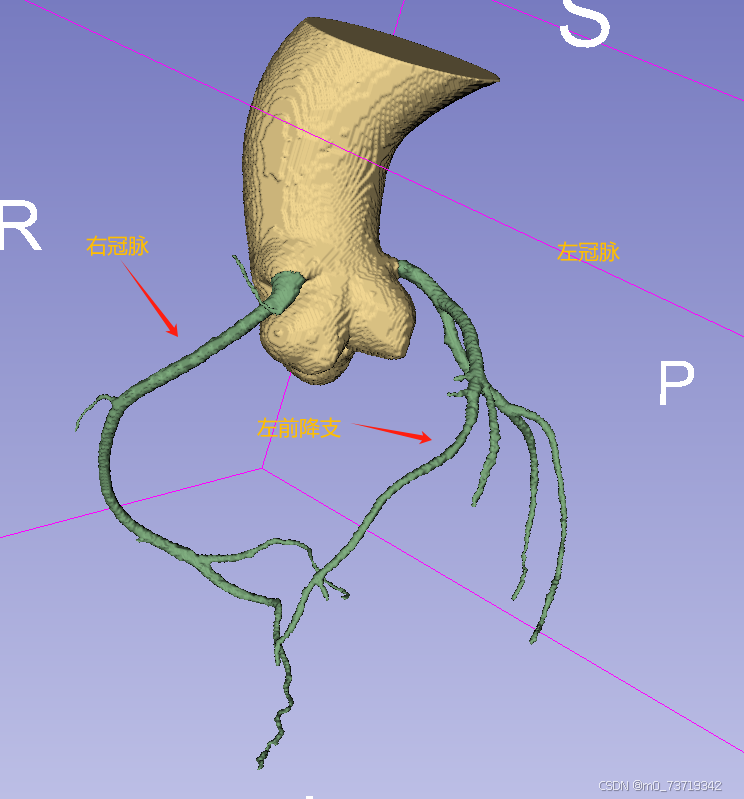

冠脉辨别如下

网络分割标签顺序(颜色无影响)